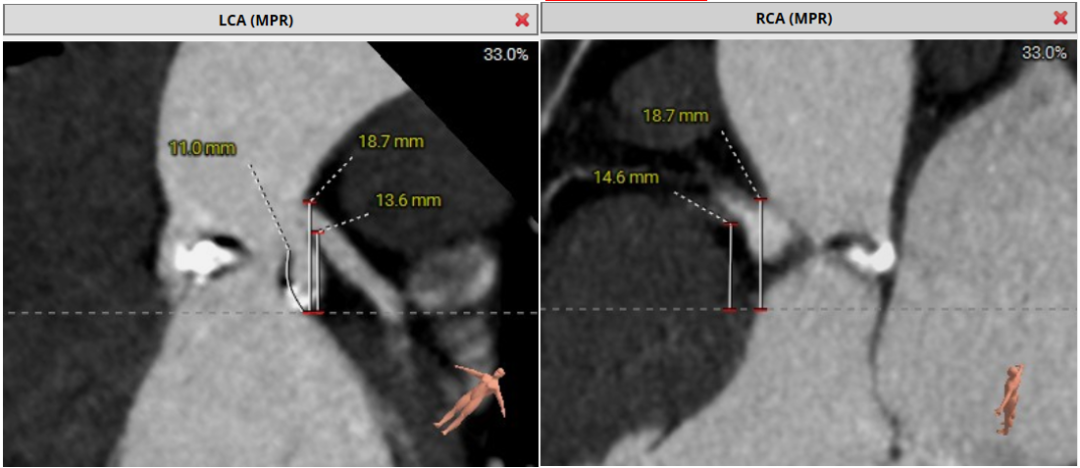

术前CT评估示:

Type 0 二叶式主动脉瓣,瓣叶增厚,中度钙化。瓣环面积376.7mm²,折算直径22.0mm,LVOT面积432mm²,折算直径23.8mm。SOV平均直径20.8mm,STJ平均直径22.3mm,高度28.8mm,

LCA 开口高度13.6mm; RCA开口高度: 14.6mm,瓣叶长度可,冠脉阻塞风险低。

升主动脉直径36.7mm; 主动脉夹角: 42°